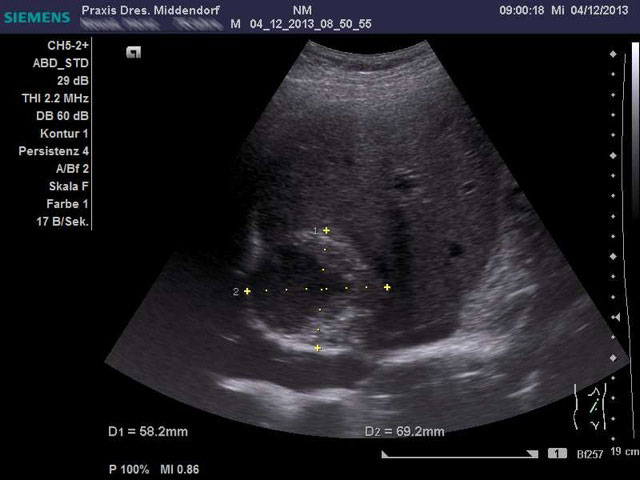

Der Ultraschall der inneren Organe ist eine der wichtigsten internistischen Untersuchungen. Viele bis dahin symptomlose Erkrankungen, die auch bei einer körperlichen Untersuchung nicht zu diagnostizieren sind, können mittels Ultraschall erkannt werden.

Eine Erweiterung der Hauptschlagader läßt sich sicher und genau darstellen. Tumore der inneren Organe wie z. B. der Leber, Niere und Bauchspeicheldrüse können im Ultraschall dargestellt werden.

Ultraschallbilder

Für eine vergrößerte Darstellung klicken Sie bitte auf eine Abbildung.